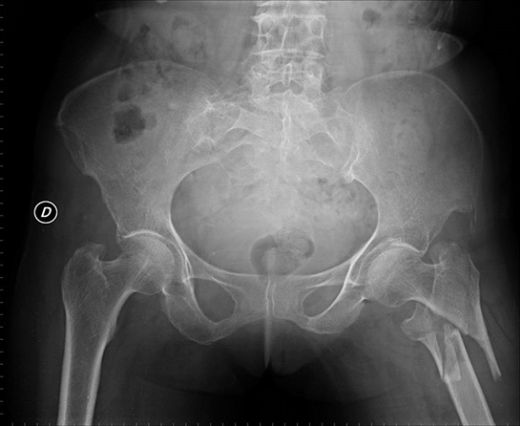

Tanı Yöntemleri Kalça kemiği çatlağının tanısı, klinik muayene ve görüntüleme yöntemleri ile konulmaktadır.

Tedavi Yöntemleri Kalça kemiği çatlağının tedavisi, çatlağın tipine ve ciddiyetine bağlı olarak değişiklik göstermektedir.